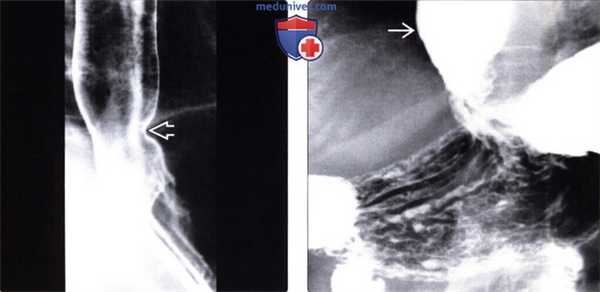

(Слева) При рентгеноскопии с контрастом у женщины среднего возраста, страдающей склеродермией, определяется дилятация и атония пищевода с наличием тугой стриктуры в области пищеводно-желудочного перехода. Пищевод медленно освобождается от бариевой взвеси, даже в положении пациентки стоя: длительное время сохраняется уровень между взвесью сульфата бария и жидкостью.

(Справа) На рентгенограмме, полученной через некоторое время у той же пациентки, определяется выраженное расширение просвета второй части двенадцатиперстной кишки с резким переходом в сужение на уровне позвоночного столба. Двенадцатиперстная кишка является вторым наиболее часто поражающимся органом ЖКТ при склеродермии; на первом месте находится пищевод.

(Слева) На рентгенограмме, выполненной во время рентгеноскопии верхних отделов ЖКТ, определяется гастроэзофагеальный рефлюкс вследствие «зияния» нижнего пищеводного сфинктера. Первичная перистальтика пищевода отсутствует. Это относительно ранние изменения при склеродермии: ни стриктуры, ни язв еще не возникло.

(Справа) На рентгенограмме, выполненной этому же пациенту в положении лежа на спине во время рентгеноскопии верхних отделов ЖКТ, определяется обратный заброс бариевой взвеси в расширенный пищевод.